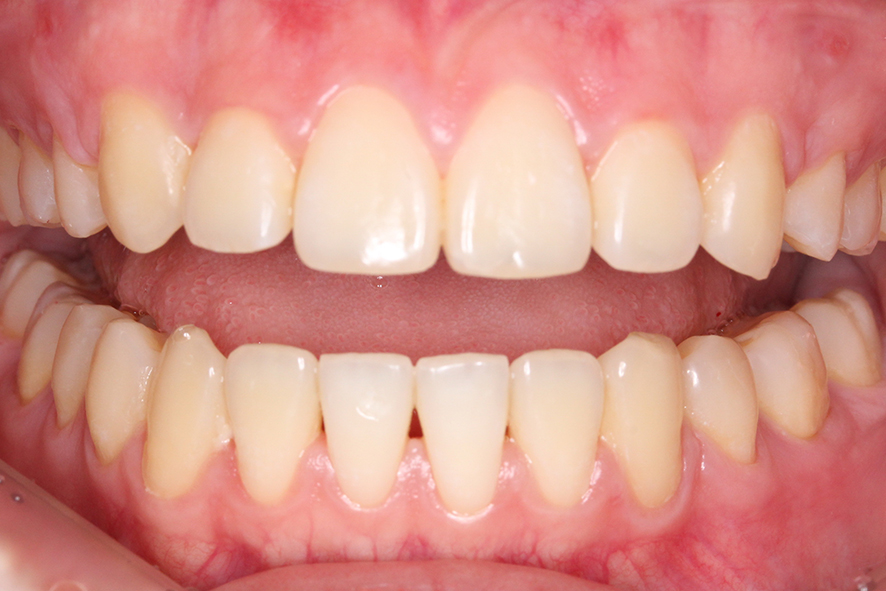

입돌출 교정 전 치아의 구내 사진을 보면

상하악을 교합했을 때 전치부의 모습이

하악이 거의 보이지 않는 deep bite

성향을 보이는 모습인데요,

상대적으로 하악의 발달이

미약하다보니 과도하게 발달한

상악으로 인해 위와 같은 증상을

보일 수 있습니다.

overbite 사진을 보면 윗니가

아랫니에 닿지 않는 모습으로

돌출감이 느껴지는 모습인데요,

정면 사진과 마찬가지로 치아의

돌출감은 심하지 않은 것으로 보입니다.